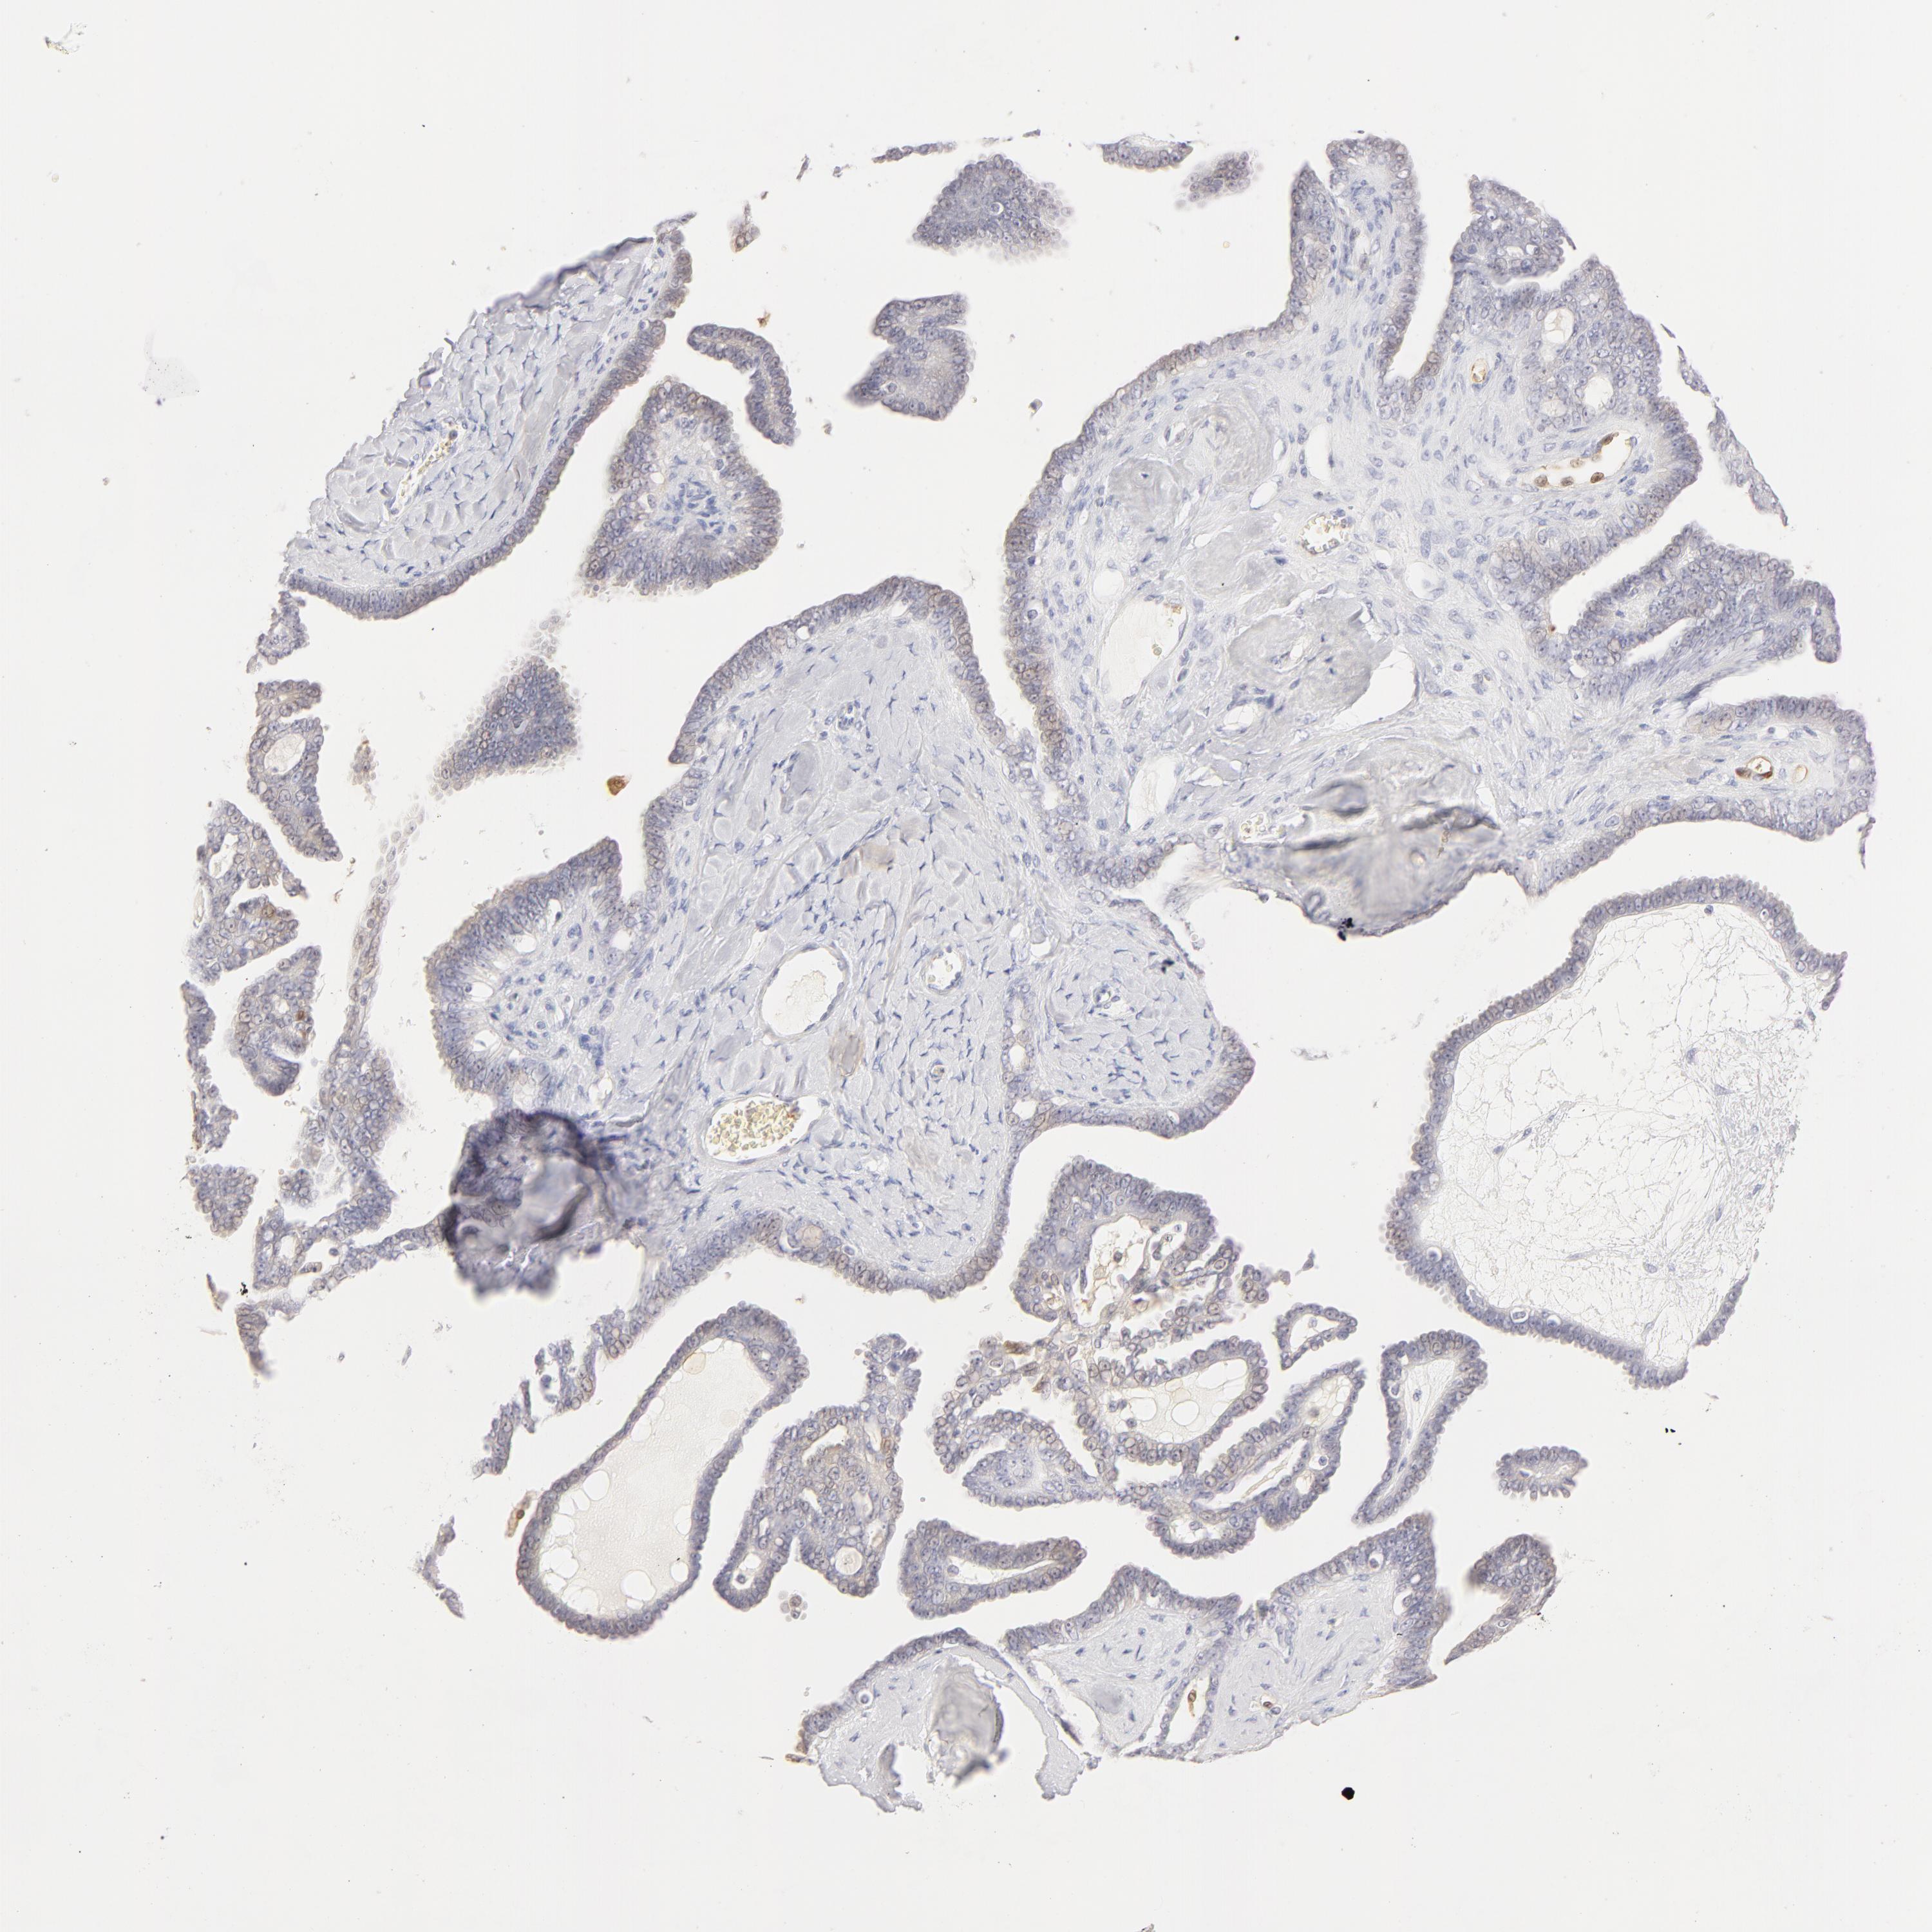

OVARIAN CANCER - Protein expressioni

A mouse-over function shows sample information and annotation data. Click on an image to view it in a full screen mode. Samples can be filtered based on level of antibody staining by selecting one or several of the following categories: high, medium, low and not detected. The assay and annotation is described here.

Note that samples used for immunohistochemistry by the Human Protein Atlas do not correspond to samples in the TCGA dataset.

Antibody stainingi

Antibody staining in the annotated cell types in the current human tissue is reported as not detected, low, medium, or high, based on conventional immunohistochemistry profiling in selected tissues. This score is based on the combination of the staining intensity and fraction of stained cells.

Each image is clickable and will lead to virtual microscopy that enables deeper exploration of all samples and also displays staining intensity scores, fraction scores and subcellular localization as well as patient and tissue information for each sample.

Antibody HPA001550

Antibody CAB010102

Carcinoma, endometroid

Cystadenocarcinoma, serous, NOS

Cystadenocarcinoma, mucinous, NOS

Carcinoma, NOS